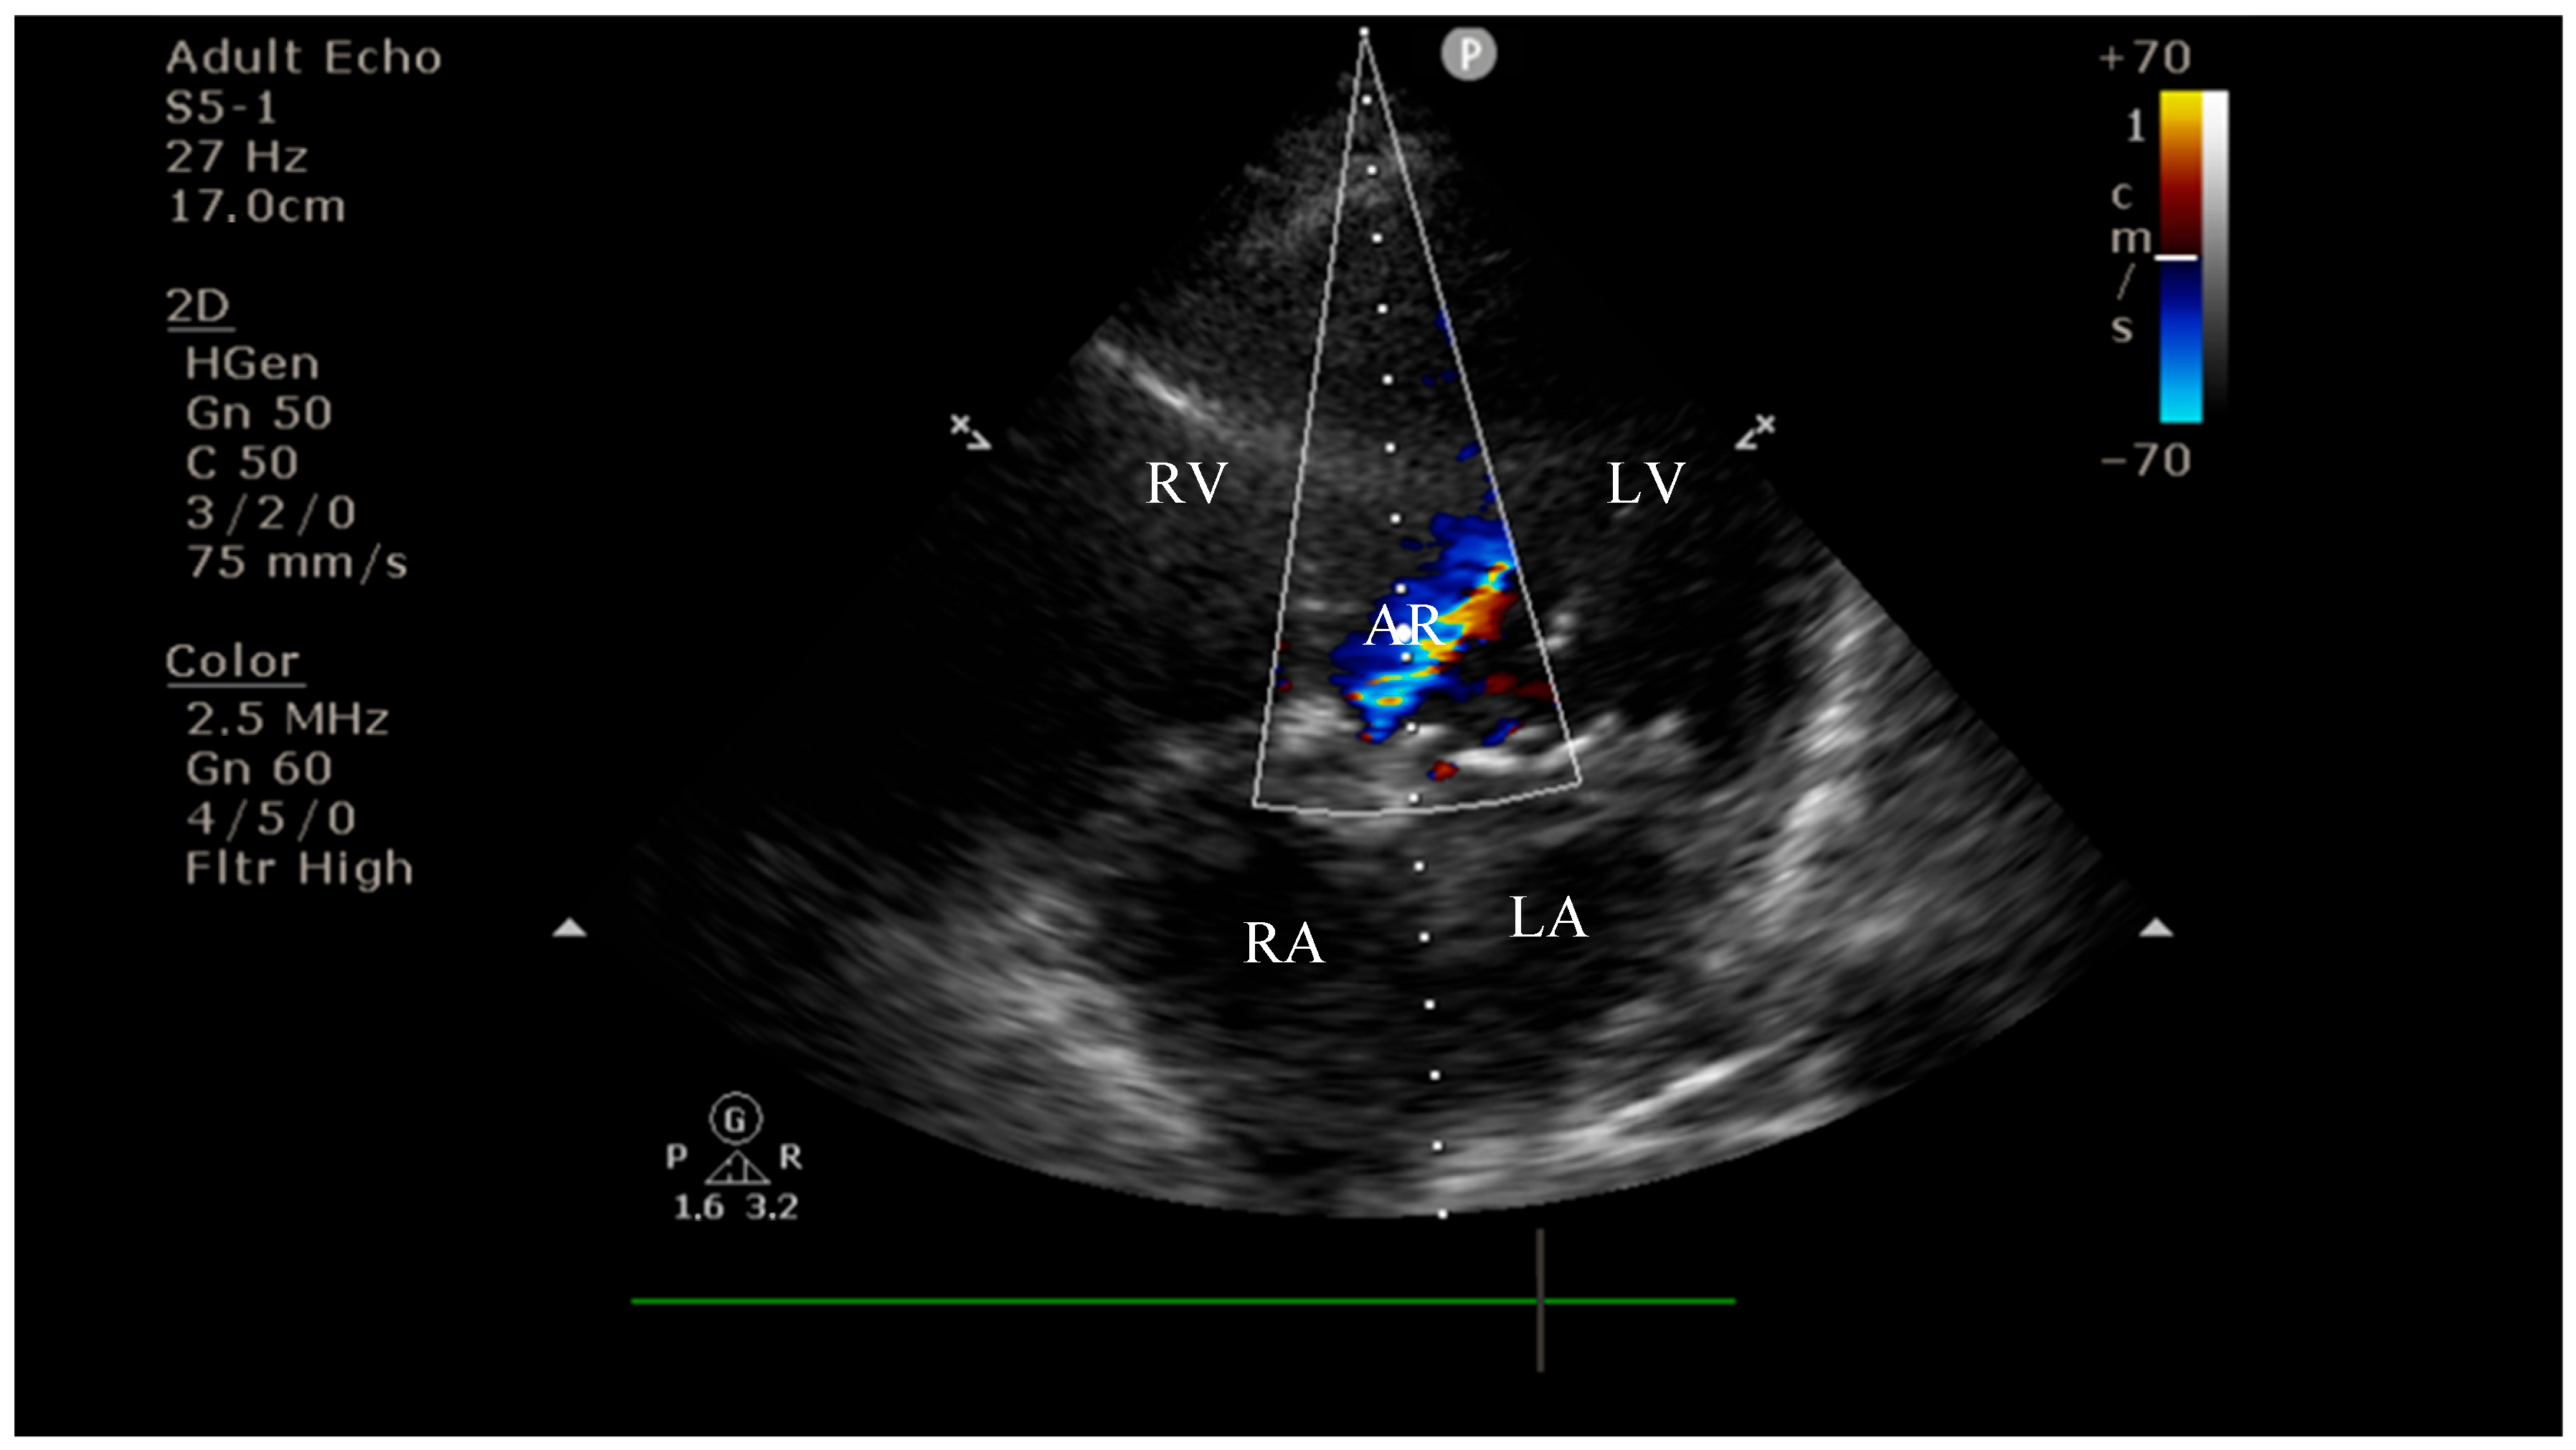

4.2. Diagnostic Findings: Mitral Valve Dysfunction and Embolic Phenomena